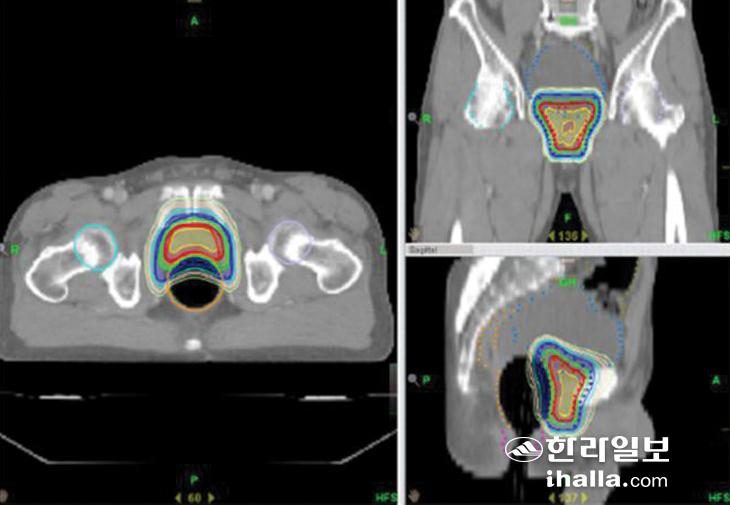

세기 조절 방사선치료(IMRT)를 이용한 전립선 암의 외부 방사선치료 설계 예시.

▶방사선 치료는=전립선 암의 방사선치료는 조기 전립선 암과 국소적으로 진행된 전립선 암 모두에서 수술 대신에 적용되거나 수술 후 남아 있을 수 있는 암 조직에 대한 치료 목적으로 사용이 가능하다. 또한 뼈 등 다른 장기로 전이가 된 경우, 이로 인한 증상 완화를 위해서도 적극적으로 활용되고 있다. 방사선치료는 외부 방사선치료(External beam radiation therapy, EBRT)와 내부 방사선 치료(Brachytherapy)가 모두 국내에서 시행되고 있다. 외부 방사선 치료(EBRT)는 선형가속기를 이용해 고에너지 방사선을 조사해 종양을 치료하는 것이다. 외부 방사선치료는 비 침습적 방법으로, 수술에 비해 비교적 신체에 부담이 덜 가해지는 치료이면서 치료 중 통증도 없다. 특히 최신의 세기 조절 방사선치료(Intensity modulated radiation therapy, IMRT) 및 영상 유도 방사선치료(Image guided radiation therapy, IGRT) 기법을 이용하는 경우, 과거에 비해 방사선 치료로 인한 치료 독성을 최소화하면서도 수술과 비슷한 치료 성적을 기대할 수 있다. 그렇지만 외부 방사선치료는 평일에 매일매일 약 1.5~2달가량 통원해 치료해야 하는 불편함이 있다.

▶방사선치료 부작용, 어떻게 관리하나=전립선 부위의 방사선 치료 후에는 전신 피로감, 조사 부위 피부의 발적, 통증, 탈모와 배뇨통, 빈뇨, 설사, 직장 출혈, 발기부전 등의 부작용이 나타날 수 있다. 그렇지만 앞서 말한 최신의 세기조절 방사선치료는 암 조직과 주요 정상 조직의 위치 관계를 고려해 조사면을 수 개에서 수십 개까지 세분화하고, 각 세분화된 영역마다 방사선의 양을 조절해 과거에 비해 보다 정밀하고 안전한 치료가 가능해졌다. 수술적 치료의 경우 피부 발적, 탈모, 직장 출혈 등의 부작용은 적으나 요실금, 발기부전의 정도가 방사선치료에 비해 심한 것으로 보고되는 경우가 있다. 따라서 전립선암에서 어떤 국소적 치료를 선택할지에 대해서는 꼭 수술을 담당하는 비뇨의학과 그리고 방사선치료를 담당하는 방사선종양학과 전문가와 함께 상의해 결정하는 것이 바람직하다.